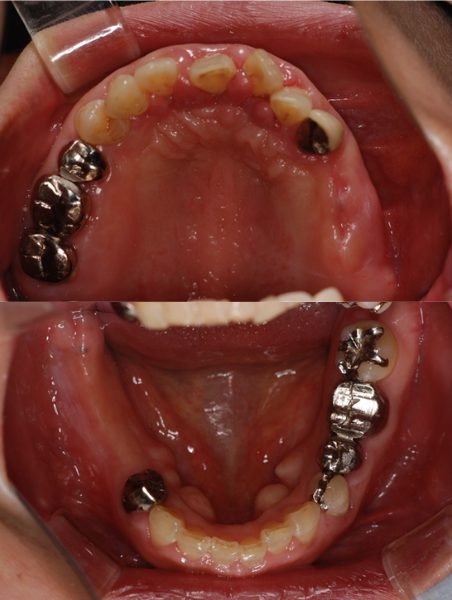

歯周病に罹患した患者さんのインプラント治療の症例①(うえだ歯科)

| 主訴 | 全顎治療希望、奥の歯茎から血が出る、綺麗で噛めるようになりたい |

| 治療内容 | 全顎的に歯周病、歯列不正が認められるため、歯周外科を含む歯周治療、矯正治療、インプラント治療、セラミックによる補綴治療後メインテナンスに移行 |

| 治療費 | 2,930,000円(税込)(インプラントすべて含む) |

| 治療期間 | 2年6ヶ月 |

| 治療回数 | 96回 |

| 想定されたリスク | 歯周病の再発、食いしばり(パラファンクション)によるセラミックの破折、歯の破折 |